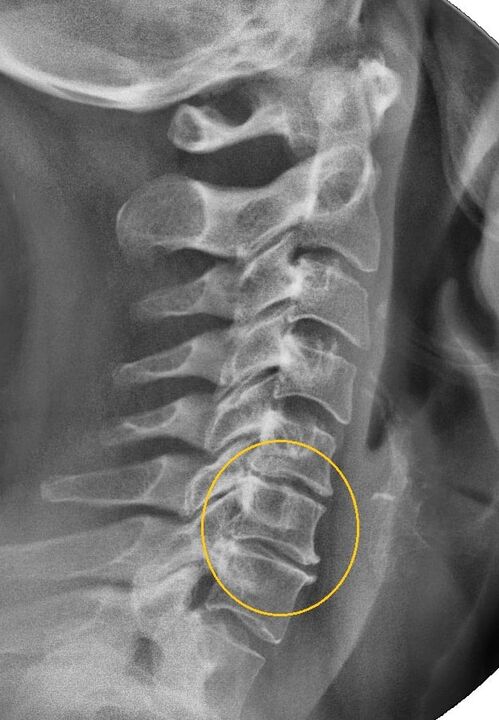

Kõige informatiivsem diagnostiline protseduur on radiograafia. 1. astme patoloogiad vastavad 1. või 2. radioloogilisele etapile. Saadud kujutised visualiseerivad haiguse tüüpilisi tunnuseid.

| I astme emakakaela osteokondroosi röntgeni etapid | Iseloomulikud märgid |

|---|---|

| 1. etapp | Väikesed muutused selgroo kõveruses emakakaela piirkonnas, mis mõjutavad ühte või mitut segmenti |

| 2. etapp | Lülisambavaheketaste kerge paksenemine, untsinate protsesside deformatsioon, lordoosi sirgendamine, luustruktuuride väikesed kasvud |